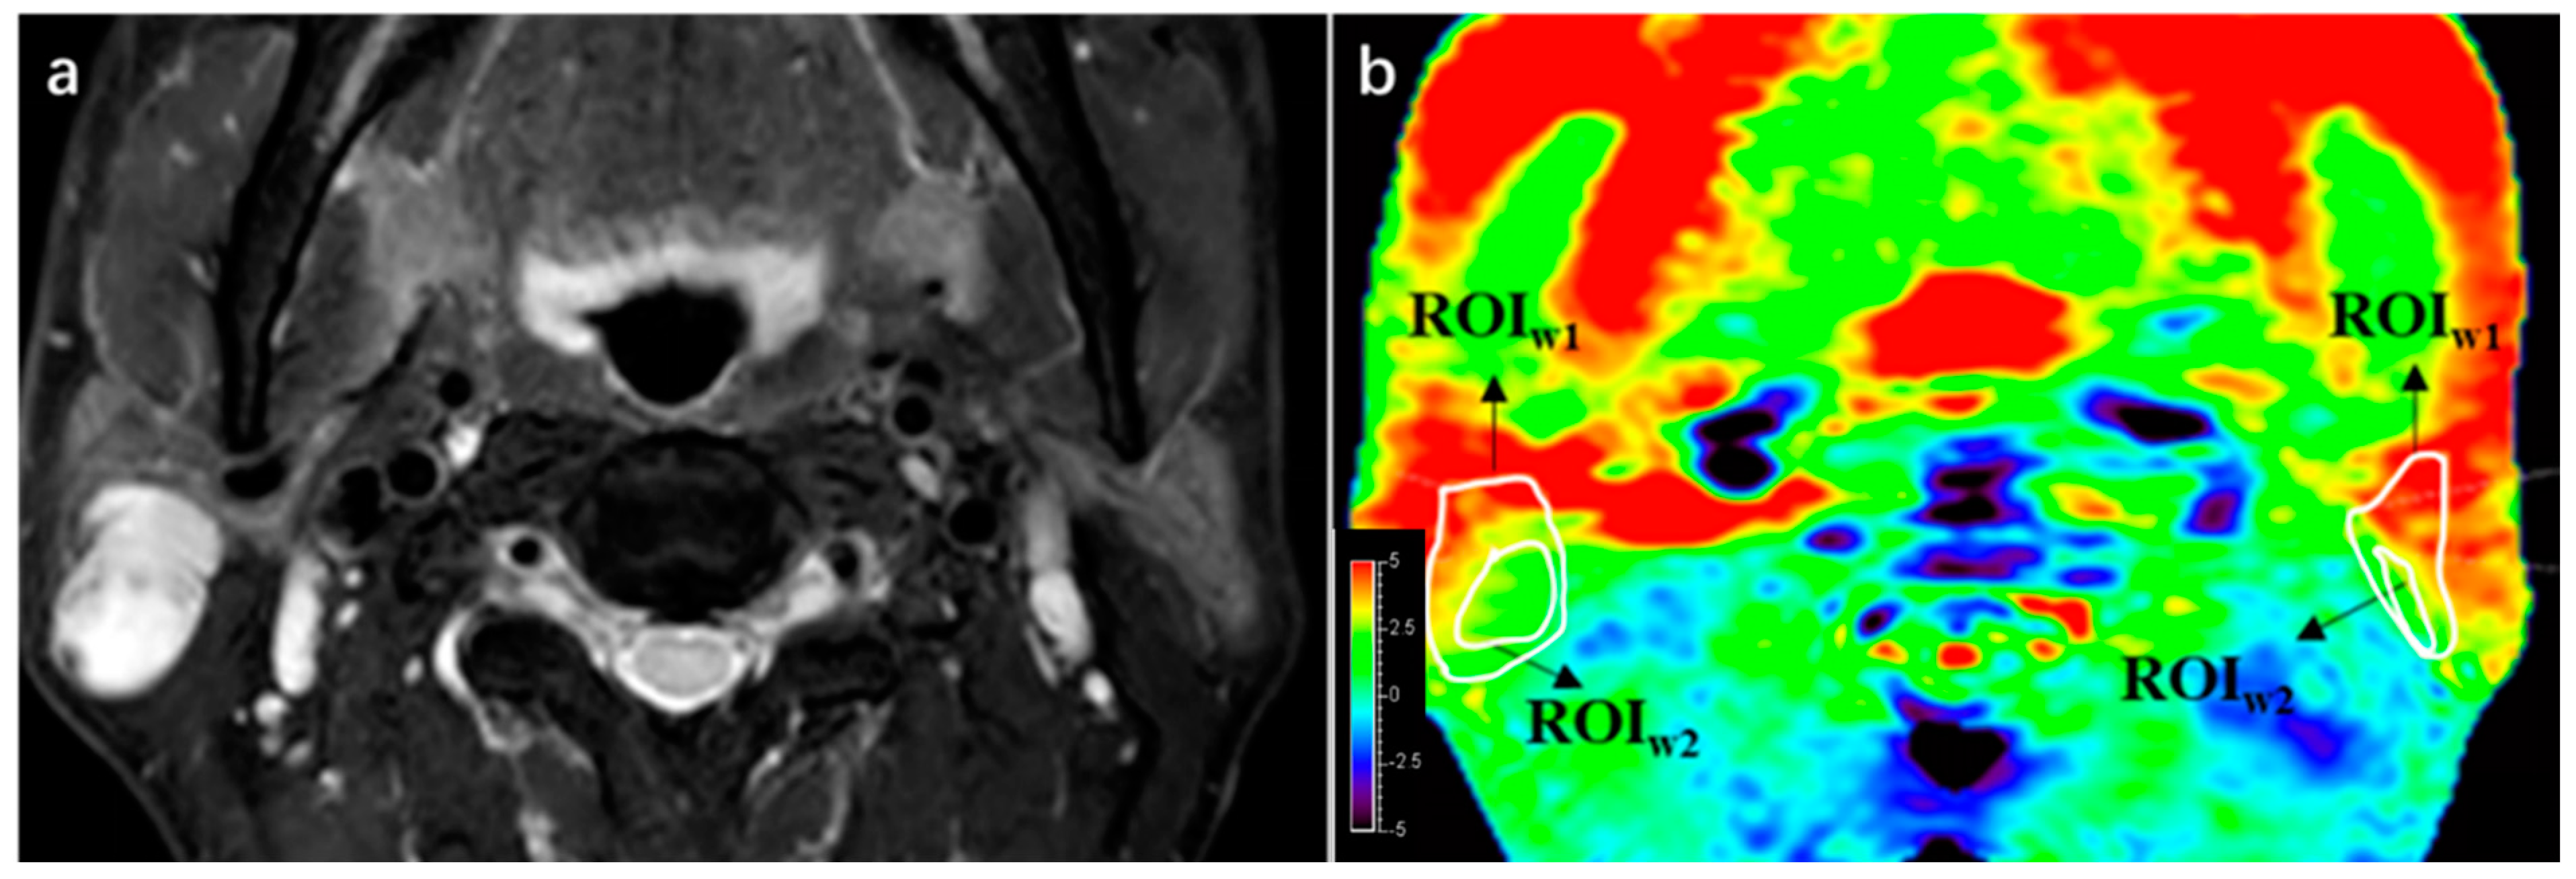

For qualitative analysis, the region of interest (ROI1) of each PG and PT was manually delineated based on the T2W images by the two radiologists. ROI2 was drawn in such a way as to maintain the most parotid gland or lesion area while excluding most of the hyperintensity artifacts (Figure 2).

Figure 2. An example of ROI1 and ROI2 drawn in a patient with WT and image quality score. (a) A lesion was found at right side of parotid gland in this 55-year-old male on T2WI. (b) ROI1 of both the lesion and parotid gland were delineated in APTw sequence 1 imaging according to T2WI, then ROI2 was drawn inside ROI1, maintaining the greatest area of normal gland or lesion while deleting hyperintensity areas. Integrity scores of both lesion and parotid were 4, considering that the entire lesion and parotid gland were displayed. Hyperintensity of lesion and parotid gland were both 3.